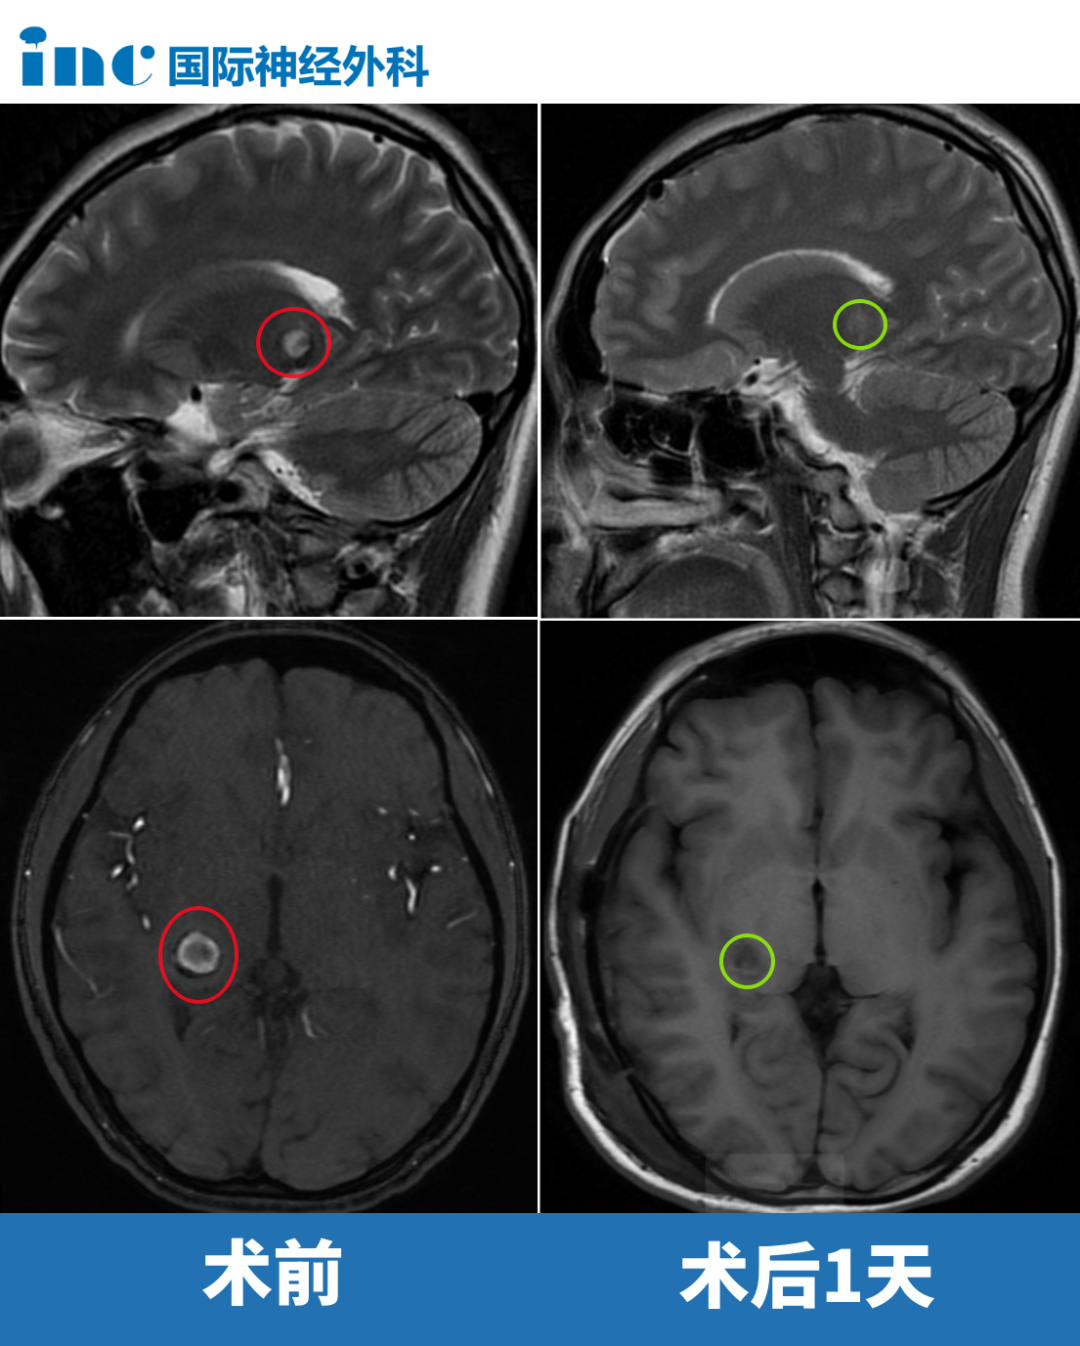

案例3:20岁女性丘脑海绵状血管瘤

术前症状:视野受限,焦点外视觉模糊,伴头痛症状

手术风险:丘脑海绵状血管瘤临床罕见,出血后常引起偏瘫等神经功能障碍,治疗极其棘手。形象比喻而言,丘脑功能类似插头转换器,若缺失此转换器,无法将信息输送至大脑。故丘脑损伤可能导致患者成为"木头人",即对外界刺激缺乏反应。对法学专业的小雨而言,此诊断犹如晴天霹雳。

术后情况:病灶完全切除,术后第一天巴教授查房时,患者恢复良好,可在病床自主活动手足。"太好了!她还是原来的她,用她自己的话说——我没有变笨,没有偏瘫,没有面瘫……"母亲激动地分享。术后3个月,患者重返校园,以全科通过的优异成绩实现完美回归。